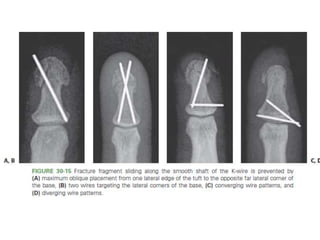

Middle Phalanx Fracture- Treatment Options

• Condylar fractures

– CRIF- converging or diverging.